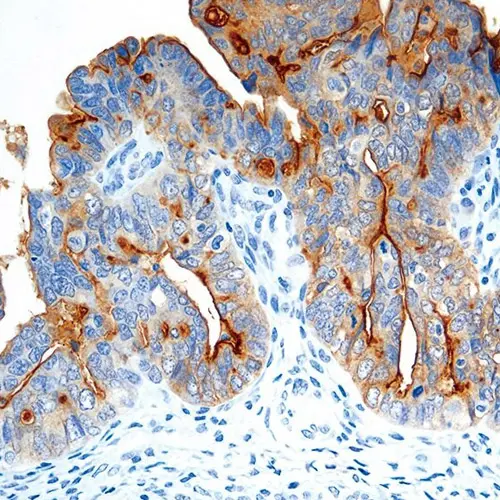

Ovarian tumor: immunohistochemical staining for Folate Receptor Alpha. Note intense cytoplasmic staining. Folate Receptor Alpha: clone BN3.2

Folatrezeptor alpha ist ein membrangebundenes Mitglied der Folatrezeptorfamilie, das den Folattransport über einen als Potocytose bezeichneten Mechanismus ermöglicht, bei dem der Rezeptor zunächst internalisiert und dann wieder zurück an die Zellmembran transportiert wird. Aufgrund dieses Mechanismus kommt es sowohl zur membranösen als auch zytoplasmatischen Färbung.